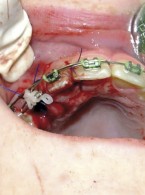

Pokrycie mnogich recesji dziąsłowych

metodą płata przesuniętego dokoronowo z wykorzystaniem przeszczepu podnabłonkowej tkanki łącznej i kolagenowego materiału ksenogennego po wcześniejszej rekonstrukcji połączenia szkliwno-cementowego - opis przypadku